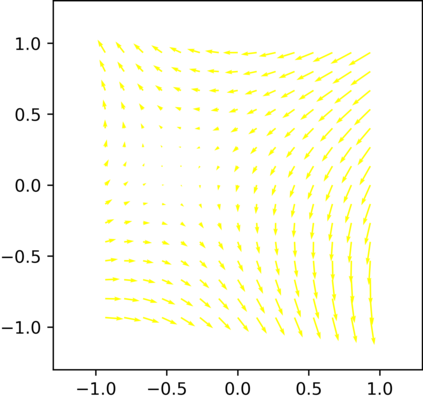

Multi-modality (or multi-channel) imaging is becoming increasingly important and more widely available, e.g. hyperspectral imaging in remote sensing, spectral CT in material sciences as well as multi-contrast MRI and PET-MR in medicine. Research in the last decades resulted in a plethora of mathematical methods to combine data from several modalities. State-of-the-art methods, often formulated as variational regularization, have shown to significantly improve image reconstruction both quantitatively and qualitatively. Almost all of these models rely on the assumption that the modalities are perfectly registered, which is not the case in most real world applications. We propose a variational framework which jointly performs reconstruction and registration, thereby overcoming this hurdle. Numerical results on simulated and real data show the potential of the proposed strategy for various applications in multi-contrast MRI, PET-MR, and hyperspectral imaging: typical misalignments between modalities such as rotations, translations, zooms can be effectively corrected during the reconstruction process. Therefore the proposed framework allows the robust exploitation of shared information across multiple modalities under real conditions.

翻译:多模式(或多通道)成像越来越重要,而且越来越普及,例如遥感中的超光谱成像、材料科学中的光谱CT以及医学中的多调MRI和PET-MR等,过去几十年的研究产生了大量数学方法,将多种模式的数据结合起来。通常作为变异性正规化的先进方法表明,在数量和质量上都大大改进了图像重建。几乎所有这些模型都基于这样一种假设,即模式已经完全登记,而在大多数现实世界应用中情况并非如此。我们提议了一个变通框架,共同进行重建和登记,从而克服这一障碍。模拟和实际数据的数字结果显示,拟议的多调MRI、PET-MR和超光谱成像的各种应用战略具有潜力:在重建过程中可以有效地纠正诸如轮换、翻译、缩影等模式之间的典型的不匹配。因此,拟议的框架允许在现实条件下,在多种模式中大力利用共享的信息。